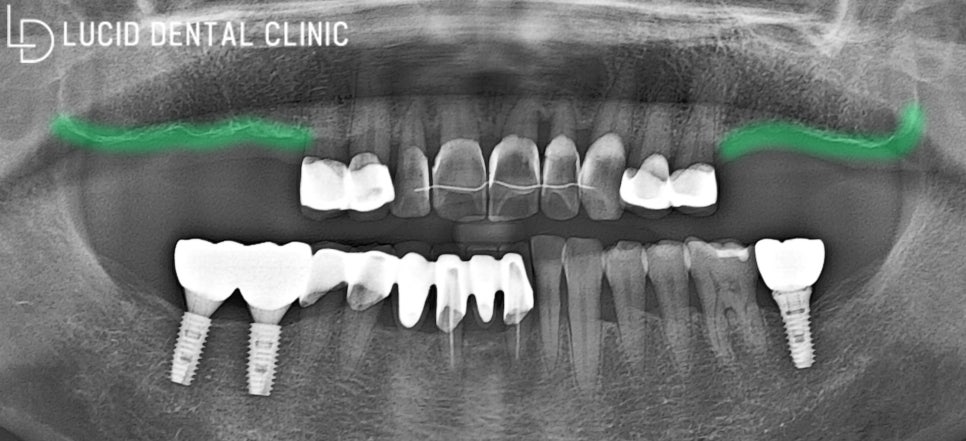

- 구강 검진의 결과는?

서초동 치과 에선 구강

전체 환경을 살펴보기 위해

초진 파노라마 엑스레이를

촬영하여 진단을 시작했습니다.

함께 촬영된 사진을 보며

내용을 설명해 드릴게요.

보이는 것과 같이 다수의 어금니가

비어있는 모습을 발견하였습니다.

게다가 발치한 지 시간이 꽤 흘러,

치조골 흡수도 일어난 상태였습니다.

이미 여러 치료를 받은 모습을 통해

환자의 구강 관리 능력이 미흡하단

사실 또한 알아차릴 수 있었죠.

앞서 설명해 드린 것과 같이

여러 문제점이 나타날 수 있어,

빠르게 치료하는 것이 좋겠네요.